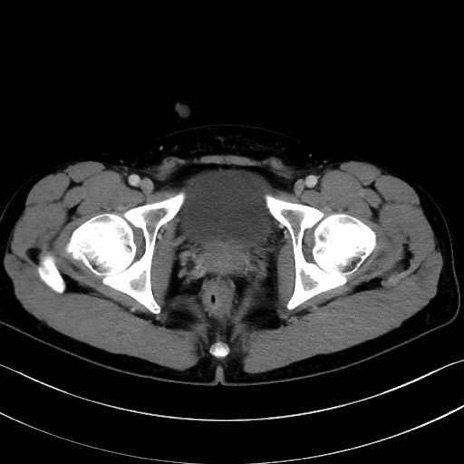

外閉鎖筋 (Obturator externus)